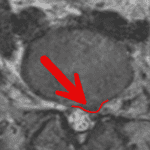

The Importance of Clinical Correlation: A Real Case Showing Why MRI Reports Must Be Interpreted Carefully

Read MoreThe Importance of Clinical Correlation: A Real Case Showing Why MRI Reports Must Be Interpreted Carefully